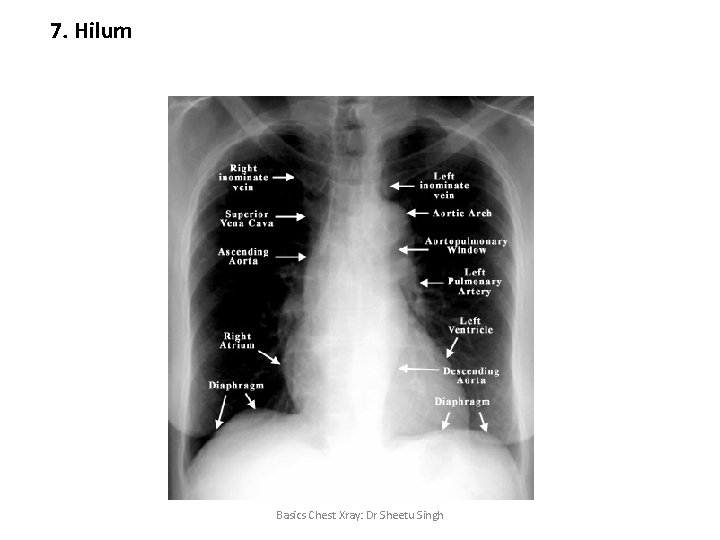

7. Hilum • • Pulmonary arteries and their main branches Upper lobe pulmonary veins Major bronchi Lymph nodes Left hilum is higher than the right hilum. Basics Chest Xray: Dr Sheetu Singh

7. Hilum Basics Chest Xray: Dr Sheetu Singh